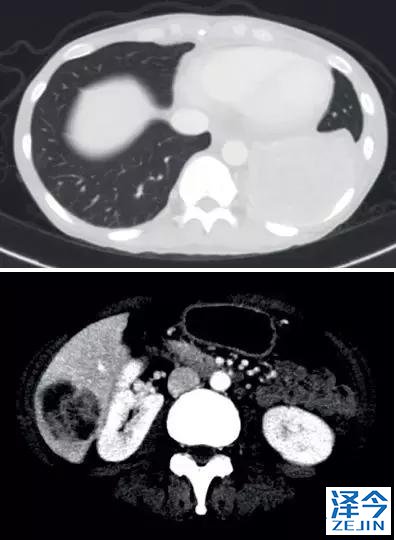

一位77岁的女性患有EPS15-NTRK1 IV期非小细胞肺癌,我们可以看到她的双肺满是病灶,并且出现了肝脏和脑转移,可以说是非常非常晚期了,

肺靶病变达到缓解,我们可以明显的看到前后的图像,病灶明显缩小了,

初始, 2018年6月 3周期 2018年8月